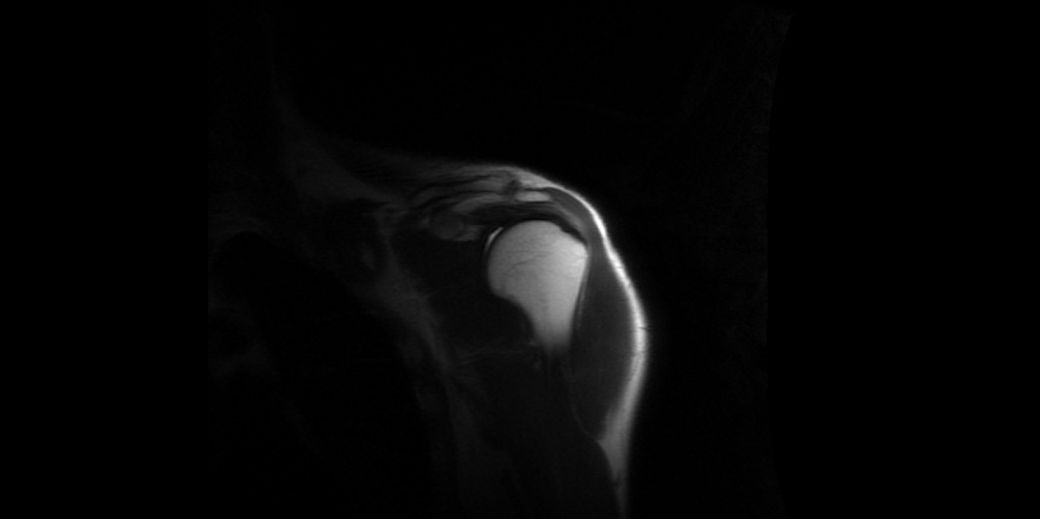

어깨 통증이 있어 mri를 찍었습니다

6월부터 어깨 통증이 있어 초음파 검사를

했고 염증이 있다하여 스테로이드 주사를 맞아 호전됐지만 한달뒤에 계속 재발하여 의사선생님이 mri를 찍어보자고 해서 찍었습니다 한 번 보시고 상태가 어떤지 알려주시면 감사드리겠습니다

MRI는 image가 많습니다.

병변 부위 병변 이외 부위 T1, T2 fat suppression등

단편적으로 올리시면 확인이 어렵습니다

판독소견을 올려주시면 그에 대하여 설명을 할 수 있도록 하곘습니다